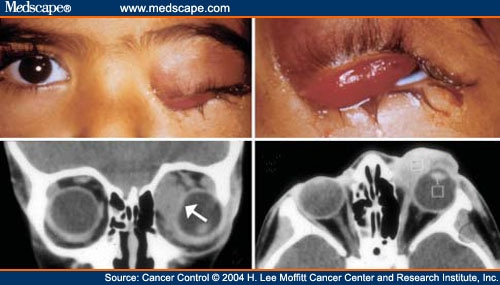

Orbital Rhabdomyosarcoma - American Academy Of Ophthalmology

rhabdomyosarcoma orbital mass

rhabdomyosarcoma cancer orbit eye

Orbital Rhabdomyosarcoma

www.medscape.com

www.medscape.com

rhabdomyosarcoma orbital